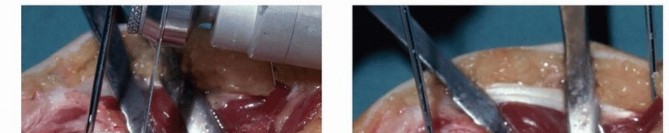

Dorsal Extra-articular Distal Radius Osteotomy: Corticocancellous Graft ### Exposure Make a longitudinal incision centered over the tubercle of Lister, in line with the third metacarpal ( TECH FIG 1A). Elevate skin flaps, taking care to protect the branches of the superficial radial nerve in the radial skin fla Incise the retinaculum over the third extensor compartment. Remove the tendon of the extensor pollicis longus (EPL) and transpose it radialward ( TECH FIG 1B). The EPL tendon will be left in the subcutaneous tissues at the completion of the procedure. Elevate the fourth dorsal compartment and its tendons subperiosteally. Preserve the integrity of this compartment. It is usually not possible to elevate the second dorsal compartment subperiosteally, so simply retract the extensor carpi radialis brevis and longus tendons radialward after opening the compartment. ### Osteotomy and Realignment Kirschner wires drilled parallel to the articular surface can facilitate monitoring of realignment ( TECH FIG 2A).

### TECH FIG 2 • A. Kirschner wires are placed parallel to the articular surface. Fluoroscopic image showing pin placement. B. The osteotomy is made with a saw as close as possible to the original fracture site. C. Lateral fluoroscopic image showing use of a lamina spreader to realign the distal fragment. D. The osteotomy has been opened and is ready for graft placement. (Copyright Diego Fernandez, MD, PhD.) A distractor or small external fixator may facilitate realignment and provisionally stabilize the fracture. The proximal threaded pin is drilled into the radial diaphysis perpendicularly in a position that will not interfere with implant application. The distal threaded pin is drilled at an angle equal to the desired correction of the lateral tilt of the distal radius articular surface so that distraction of the two pins will bring this pin parallel to the proximal pin (perpendicular to the radius), thereby restoring alignment. The pins should be drilled so that they also help restore the appropriate ulnarward inclination of the distal radius articular surface when distracted. Planned angular corrections can be monitored with sterile geometric templates. The osteotomy is made parallel with the distal Kirschner wire and as close to the original fracture site as possible using an oscillating saw ( TECH FIG 2B). If the fracture is not yet completely healed (nascent malunion— usually within 4 months of injury), recreate the original fracture line by carefully removing fracture callus at the fracture site. This callus can be saved and used as bone graft. If the fracture is solidly healed, attempt to identify the prior fracture site. If this is uncertain, choose a site that creates a distal fragment large enough to facilitate manipulation and internal fixation while trying to stay distal enough to take advantage of the healing capacity of metaphyseal bone. A lamina spreader can be used to help realign the distal fragment as well ( TECH FIG 2C,D). Care must be taken when operating on osteoporotic bone. Additional provisional stability can be provided by placing 1.6-mm smooth Kirschner wires. If the ulnar variance can be restored with angular realignment alone, the volar cortex can be cracked and hinged open in an attempt to maintain some stability of the osteotomy. If lengthening of the volar cortex is required to restore ulnar variance, a second distractor in another plane (eg, direct radial) may prove useful for obtaining and maintaining alignment. ### Graft Insertion and Fixation Once the osteotomy is created and the radius realigned, bone graft is inserted. Harvest bone graft ( TECH FIG 3A). Either a corticocancellous (structural) bone graft or cancellous bone graft can be used. Potential advantages of a structural graft include immediate structural support ( TECH FIG 3B) and the possibility of using a smaller implant and thereby avoiding tendon irritation. A cancellous (nonstructural) bone graft can be harvested using trephines ( TECH FIG 3C). This avoids tedious, difficult, and unpredictable harvest and contouring of corticocancellous grafts as well as the morbidity associated with harvest of a standard iliac crest bone graft. Apply a single T- or Pi-shaped plate or two 2.0- or 2.4-mm plates (one applied dorsally, ulnar to the tubercle of Lister, and 147 the other applied radially between the first and second dorsal compartments).